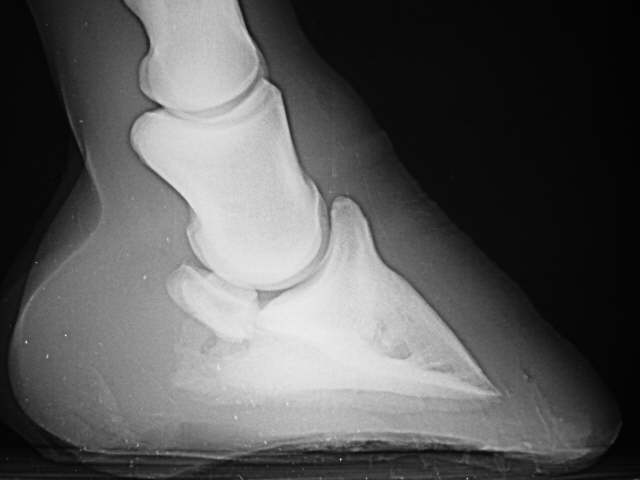

Sinker

Abgesunkenes Hufbein. Die Haltestruktur des Hufbeins in der Hornkapsel ist zerstört.